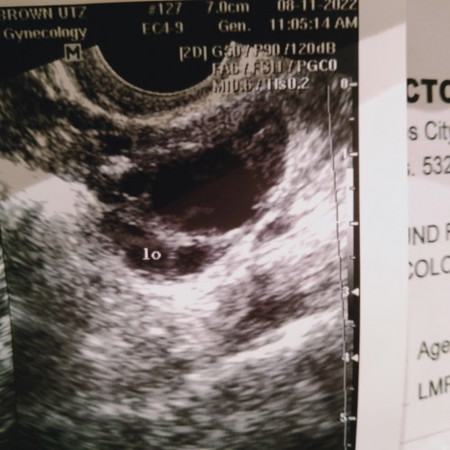

According to my OB need lang namin ni Hubby mag make love sa Aug. 10 -15 para kami ay makabuo dahil nakita nila sa transvaginal ultrasound ko na may isang egg (ovulate) . Aug 22 (ngayon) nag pt ako pero negative pa rin.. possible bang buntis na ako pero ndi pa madetect ng HCG mga 4 weeks and 1 day na po ako according to LMP.. nakita ko sa app na ito mga August 28 ako mag pt mga 5weeks na ako nun .. sino po dito na kagaya ko mga mi, please help naman po and gusta ko lang pong malaman mga experience sa pregnancy journey nyo. THANK YOU 🙏 Yun nasa picture ay transvaginal ultrasound ko nun pumunta kami, yan po egg ko sa left ovary.. #advicepls #pleasehelp #pregnancy #respect_post #respect